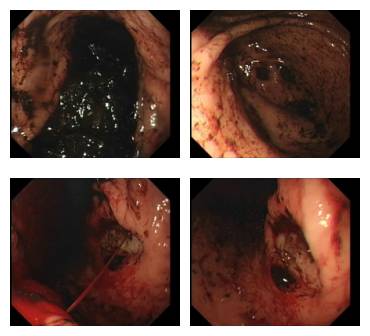

第一次内镜下止血

患者急性消化道大出血,扩容补液后血压、脉搏还算平稳,急诊胃镜进镜后发现整个胃腔全是积血,到哪找出血部位啊,我深吸一口气冷静了一下,给予负送水及抽吸胃内积血后,发现在胃角有一处不规则深凹陷,中央喷射状出血呈一条血柱,立即给于去甲肾+生理盐水喷注出血部位,出血暂时止住了,但考虑胃癌可能,当时告知外科医生及患者家属,其家属商量后要求急诊手术,后来病理证实的确是胃癌。

体会:遇到急性出血的患者内镜诊治一定要胆大心细。